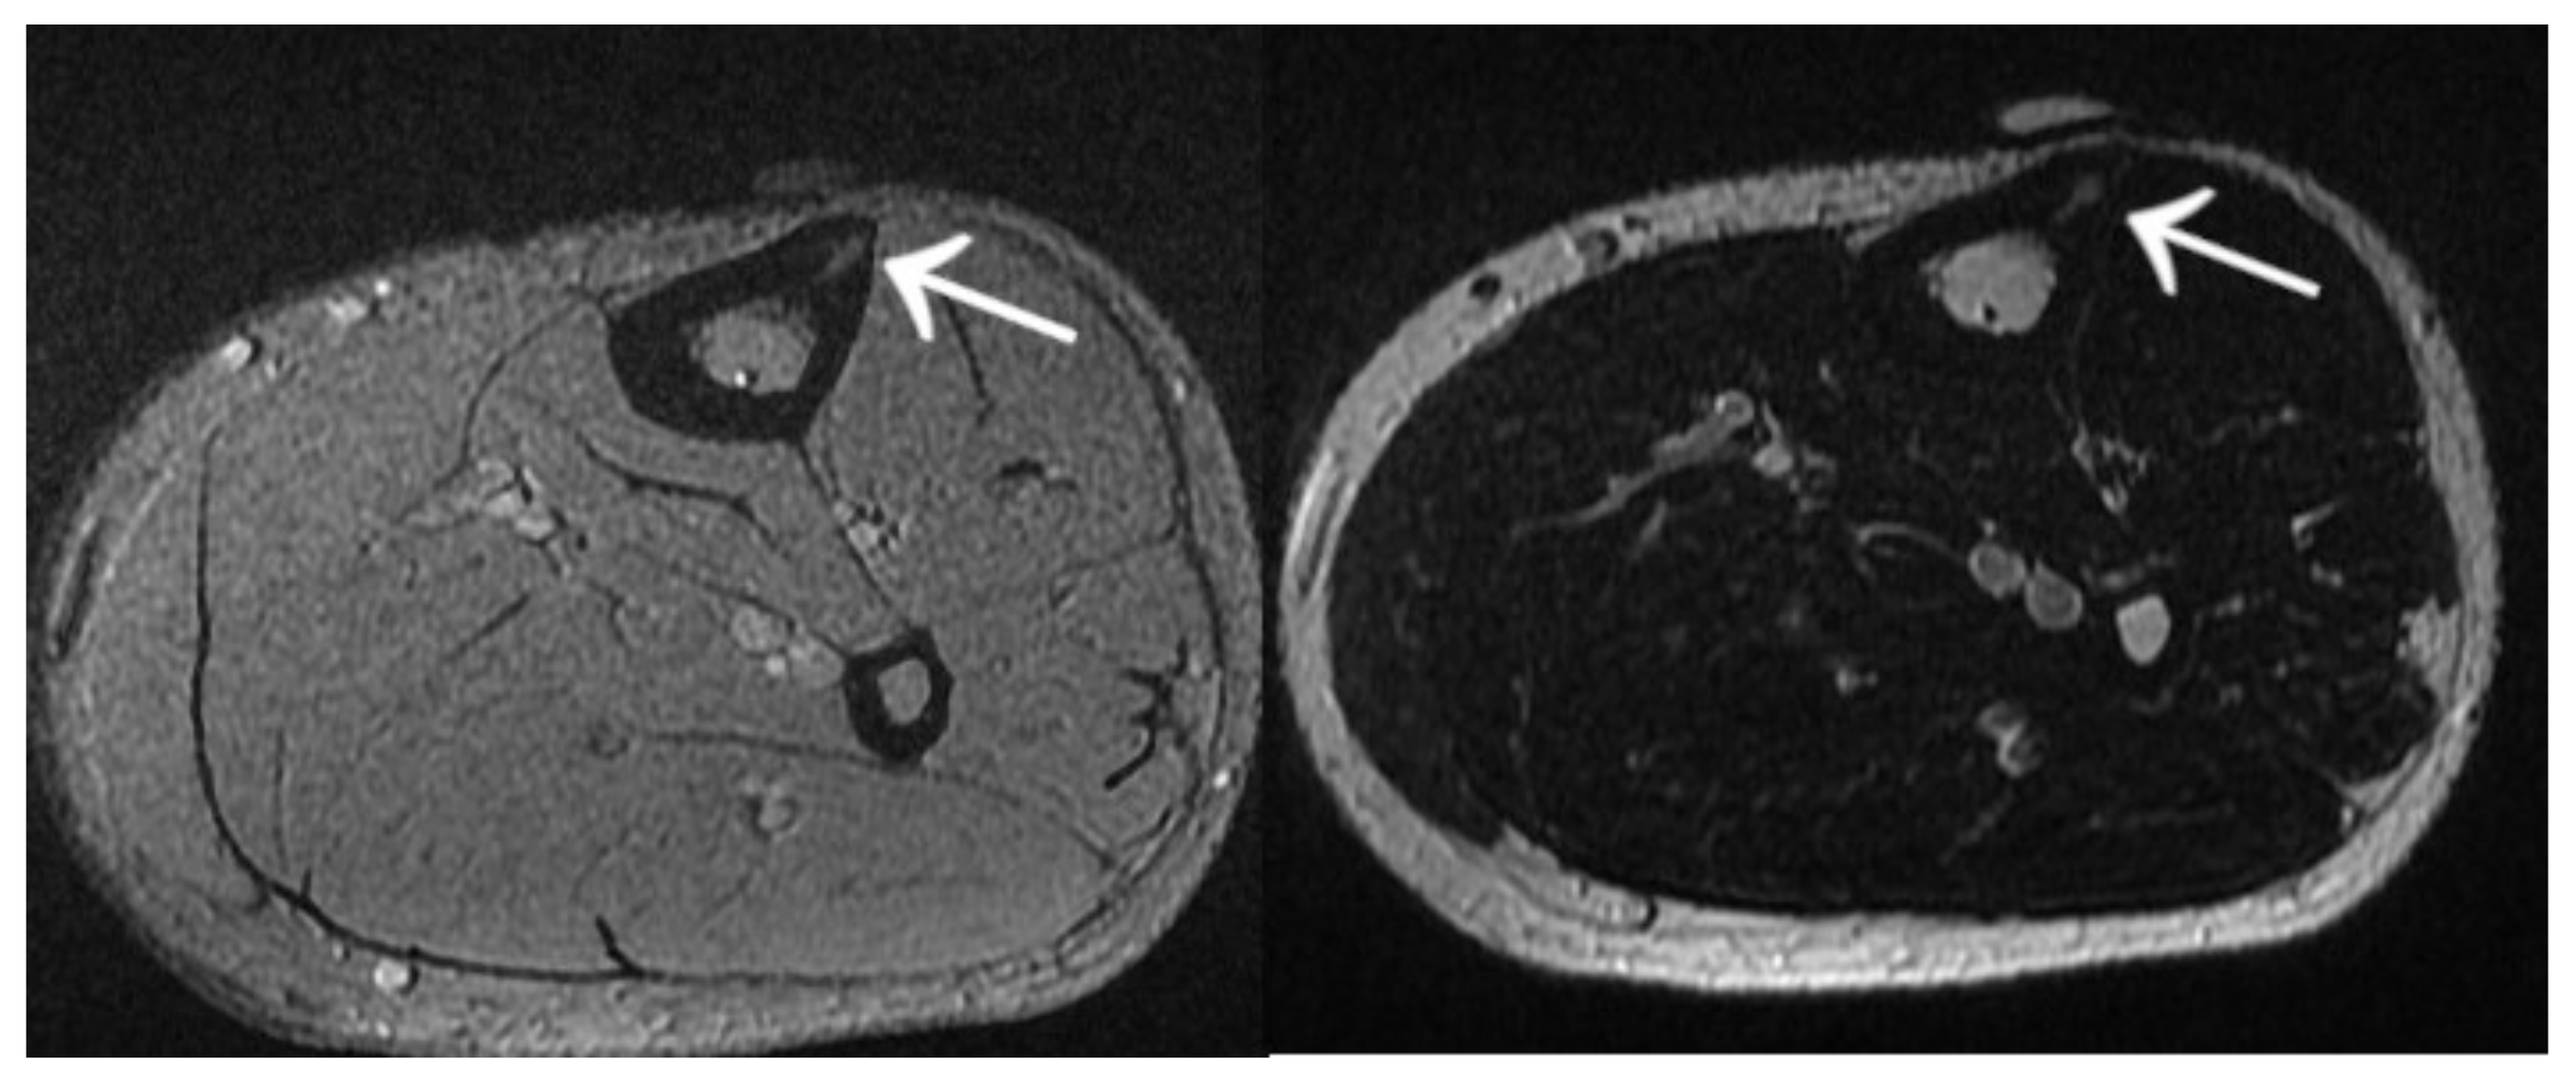

Figure 20.

MRI scans showing a focus of OO (arrows) in the left tibia.